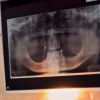

A Clínica Jeniffer Degasperi Odontologia, em Santa Helena, reforça seu compromisso com a saúde bucal com o atendimento do Dr. Alciney de Almeida Luiz (CRO/PR 11.127), mestre e especialista em Implantodontia.

O profissional atua com foco em implantes dentários, avaliações, manutenção e acompanhamento personalizado, oferecendo segurança, precisão e orientações claras em cada etapa do tratamento.